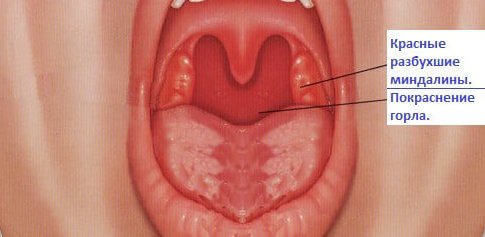

На изображении показано, как изменяется слизистая оболочка горла при вирусной ангине.

С помощью фото, представленного выше, можно увидеть разницу между проявлениями бактериальной формой ангины и вирусной.

Симптомы могут варьироваться в зависимости от типа ангины. Вирусная ангина проявляется острым воспалением горла, болью, покраснением и отеком миндалин. Многие пациенты отмечают стремительное развитие симптомов, иногда всего за несколько часов. В отличие от бактериальной ангины, вирусная форма чаще не требует антибиотиков, акцент делается на симптоматическом лечении. Рекомендуются полоскания с солевым раствором, теплые напитки и леденцы для горла для облегчения дискомфорта. Популярны противовоспалительные средства, такие как ибупрофен или парацетамол, для снижения температуры и уменьшения боли. Важно помнить, что при вирусной ангине организм обычно справляется с инфекцией самостоятельно, поэтому следует сосредоточиться на отдыхе и поддержании водного баланса.